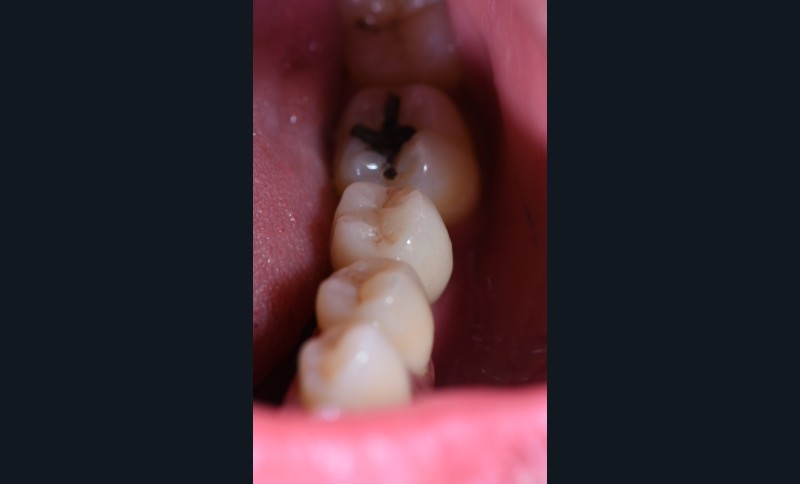

3 mois après cicatrisation , nous reprenons notre camera en main, et cette fois ci, nous allons prendre l’empreinte de notre « scanbody » qui est le transfert d’empreinte numérique (fig. 4) correspondant à notre implant (Megagen). C’est la que la magie opère… Fini les portes empreintes individuels, à perforer etc. On place le scanbody et on prends l’empreinte (haut , bas , occlusion). On peut même prendre le profil d’émergence sur un scan supplémentaire en quelques secondes.